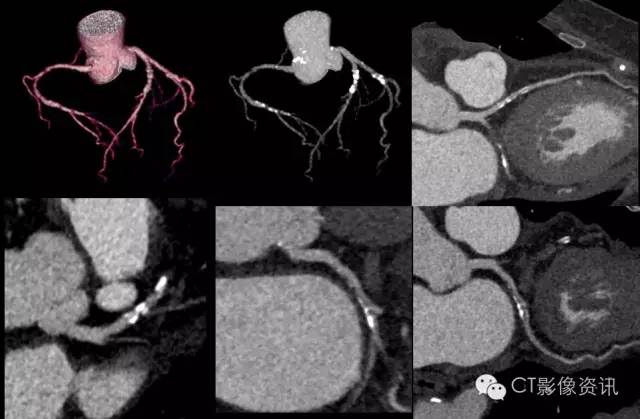

这可是85kg/170cm身高的超重大体型,他的心脏血管怎么样?非常漂亮的没有问题的血管!

这个检查只用了0.39mSv就完成啦!这可比传统CT的扫描动辄7-10个mSv的剂量低了太多!这是常规胸片剂量!Revolution CT亚mSv冠脉扫描可是常规工作状态啊!

以上都是常规的心率患者,心率高的患者Revolution CT表现如何哪?

同样的这样的检查在探测器宽度不够宽的设备上需要多个心跳才能完成。而每多一个心跳的曝光,就意味着更多的辐射剂量,现在咱们的Revolution CT可以直接像做体检一样进行!One Beat不再是一个目标,是每天常规进行的检查!

Revolution CT还有一双工作站慧眼,帮我们更准确的找到很小的小斑块。提供了冠脉探针以及类血管内超声的技术,帮助我们评估斑块的类型。您看,如下的局限性的小斑块依然无所遁形!